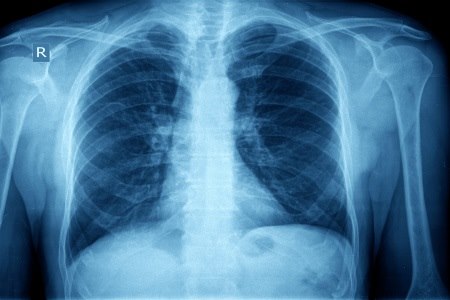

צילומי החזה הסטנדרטיים משמשים למטרות מיקוד האבחון. צילום: thinkstock

צילומי חזה מבוצעים על פי רוב כאשר מטופלים מגיעים עם תלונות חריפות או כרוניות הקשורות למערכת הנשימה. צילומי חזה נחלקים לשני סוגים עיקריים: צילומי רנטגן "פשוטים" סטנדרטיים וצילומי CT.

לרוב, צילומי החזה הסטנדרטיים משמשים למטרות מיקוד האבחון, כחלק מהאבחון הכללי - הכולל גם התייחסות לתלונות ולהיסטוריה רפואית, בדיקה פיזית של המטופל ובדיקות מעבדה שונות - אך בדרך כלל אינם עומדים ככלי אבחוני, בפני עצמם.